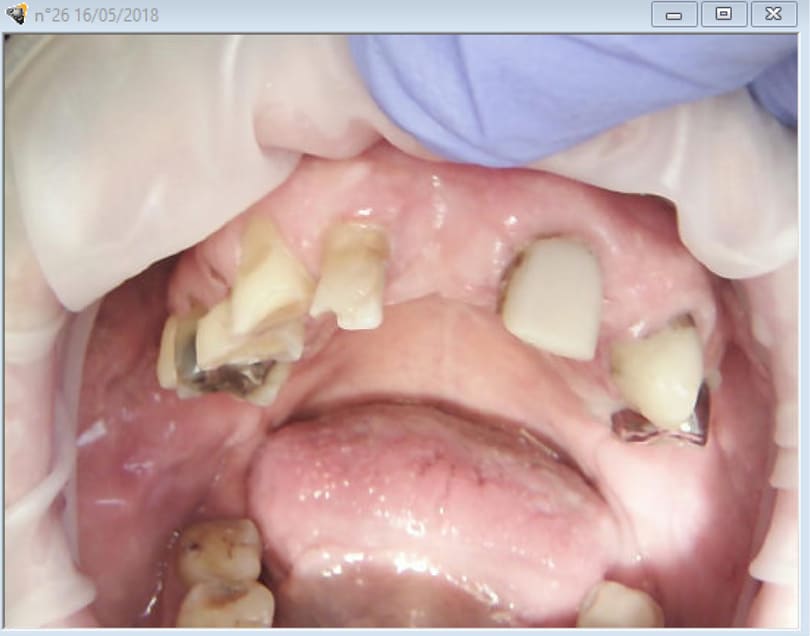

2 stellites one shot. Ca fait 8 mois que je fais des empreintes optiques et je ne suis toujours pas fier quand j'ai ce genre d'empreintes à faire.

Empreinte d'étude. En vue quelques cerams + stellite haut le tout one shot.